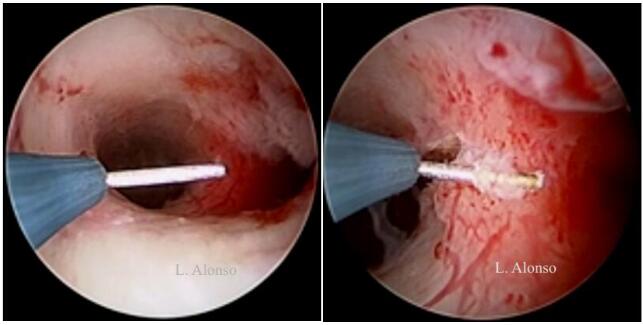

宫腔镜子宫成形术是在子宫纵隔上划开一个横行切口取代了切除。这个切口应在纵隔中间划开,与宫腔前后壁距离相等。参照输卵管开口进行手术有助于保持切口水平,避免损伤正常子宫肌层。选择正确的切口位置是宫腔镜子宫成形术最重要的一部分,但是选择合适切口并不容易。Levent Yasar 和 Ali Süha  发现在亚甲蓝注射后,有2-3mm的蓝色的线,在输卵管开口之间跨过纵隔并且与宫腔前后壁等距离,称此为“Süha-Levent 线” 。这条蓝色的线可以帮助他们选择正确的切口位置。

发现在亚甲蓝注射后,有2-3mm的蓝色的线,在输卵管开口之间跨过纵隔并且与宫腔前后壁等距离,称此为“Süha-Levent 线” 。这条蓝色的线可以帮助他们选择正确的切口位置。

纵隔手术有两种不同的手术方式,薄化技术和缩短技术。薄化技术是在子宫的每一面将纵隔从底部到顶端做纵行切口,目的是减少纵隔的宽度并改善初始宫腔两侧宫角凹陷中间的基底部残余组织。在缩短技术中,纵隔被横向由顶到底的切开,切口位于纵隔中间,向宫腔前后壁切除残余组织。